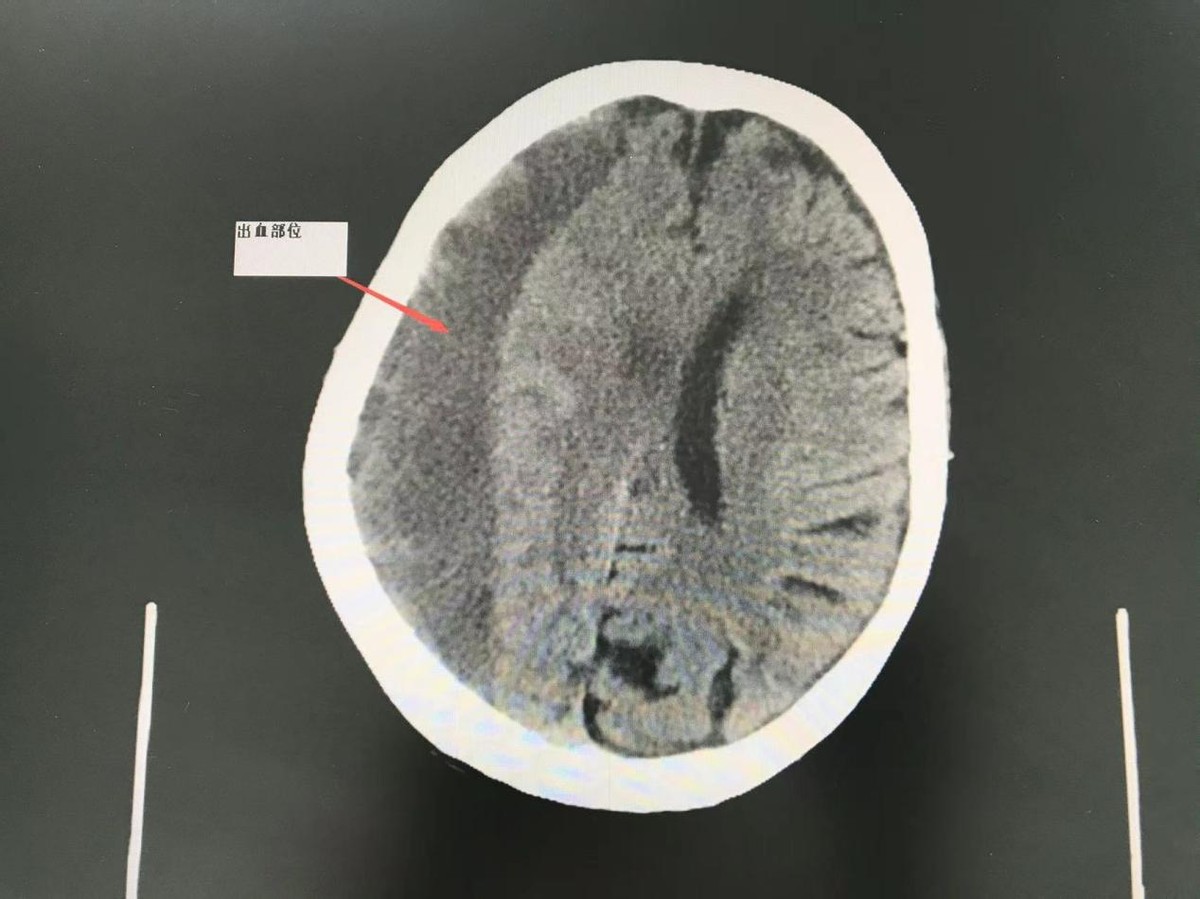

93岁的刘奶奶最近几天走路时发生左侧肢体无力、走路不稳的现象,遂来犍为县人民医院就诊。神经外科综合病史、查体及影像学检查,诊断为:慢性硬膜下血肿。经多学科充分会诊,深入讨论,拟行脑钻孔清洗引流术。

慢性硬膜下血肿多数由轻微的头部外伤引起口血肿可缓慢增大,一般3周以后才出现症状。老年人易发生硬膜下血肿的原因可能与动脉硬化、血管脆性增加、脑血管容易损伤有关。且由于脑萎缩、颅腔间隙增大,为血肿的扩大提供了较大的空间,在一定的时间内症状不明显。该病的常见症状是头疼、头胀、头晕、 智力下降、语言不流利、肢体活动障碍及癫痫发作等。严重者可昏迷,甚至因发生脑疝而危及生命。该病与脑血栓、脑萎缩、老年性痴呆、脑肿瘤等疾病有某些相似之处,故其早期易被误诊,导致治疗延误。通过头颅 CT 和磁共振(MRI)检查,可以确诊该病。对于有临床症状的慢性硬膜下血肿,应尽早施行手术治疗,可使绝大部分慢性硬膜下血肿患者迅速康复。